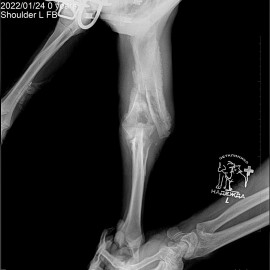

Наш пациент пёс по кличке Малыш. Обратились к нам в клинику с жалобами на хромоту на переднюю левую лапу. Был проведен осмотр и рентгенологическое исследование, после которого был поставлен диагноз: состояние после перелома левой плечевой кости. Была проведена операция: остеосинтез левой плечевой кости.

Снимок 1-2 до операции.